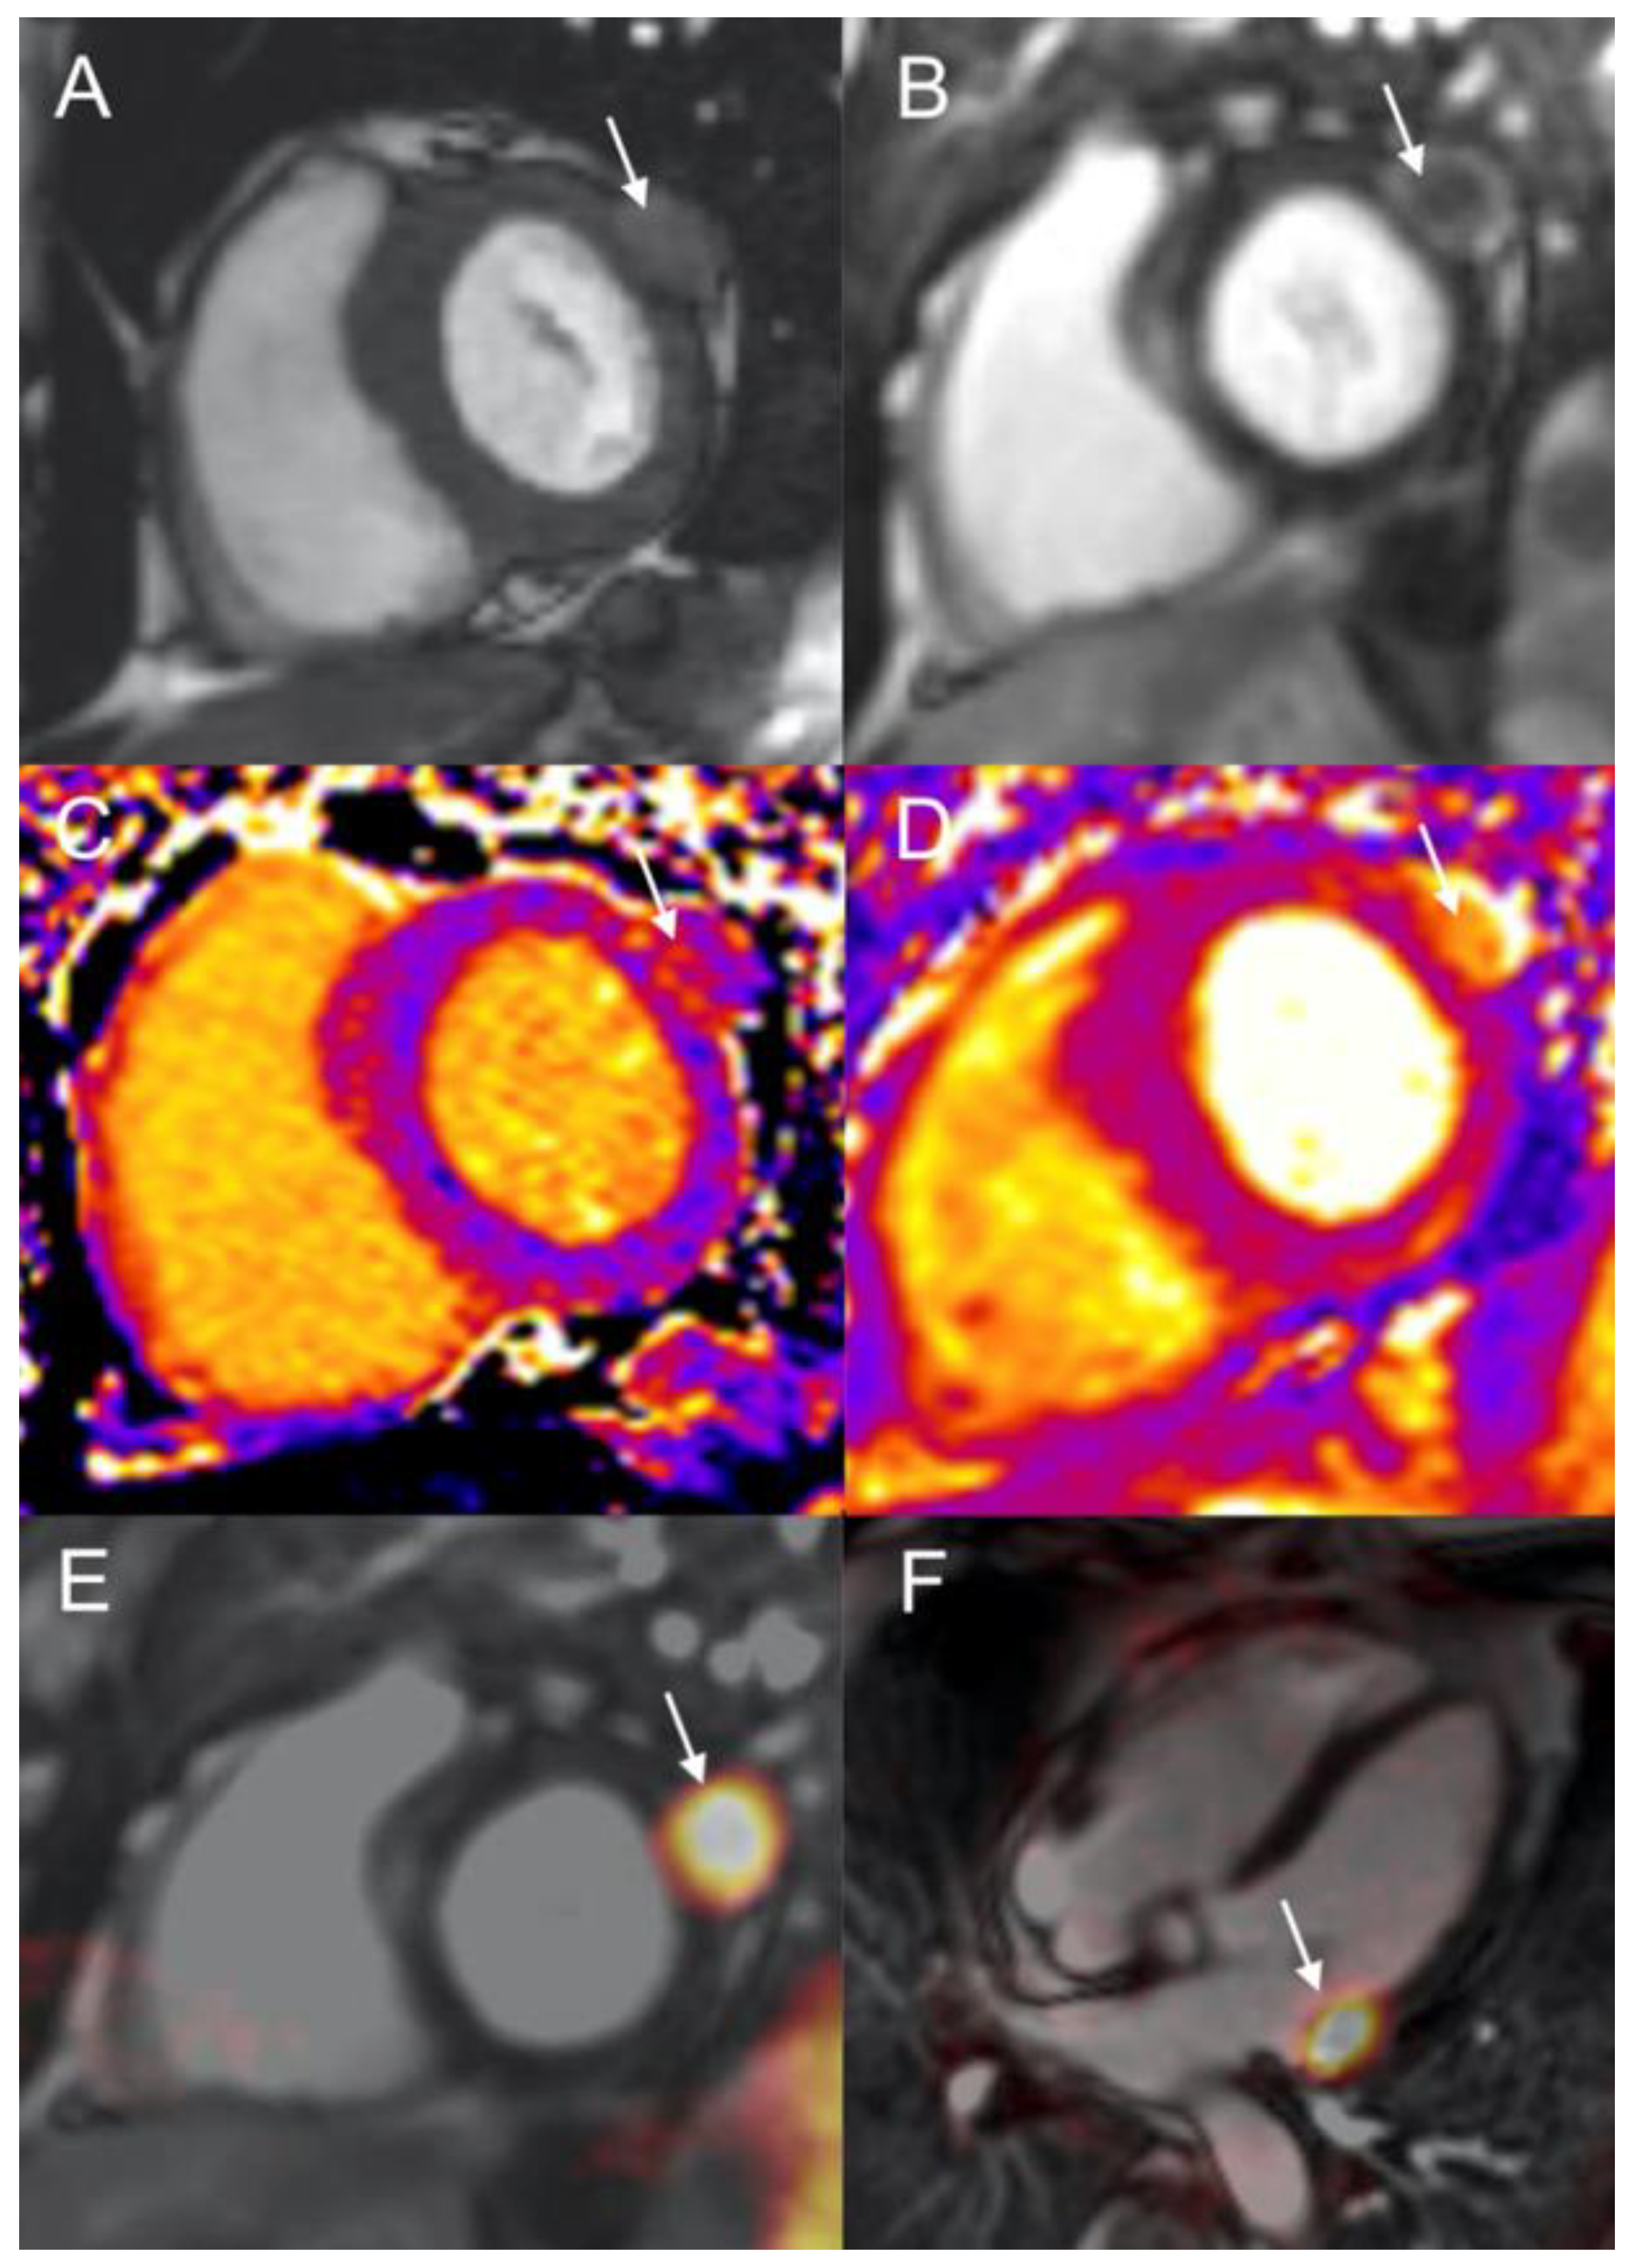

2.3. Patient 3

- CMR and Cardiac-CT enable high-resolution, multiplanar imaging crucial for accurate anatomic localization, mass mobility assessment, and tissue characterization for noninvasive diagnosis confirmation;

- PET/MRI could represent a possible efficient “one-stop-shop” solution in patients with si-NETs.